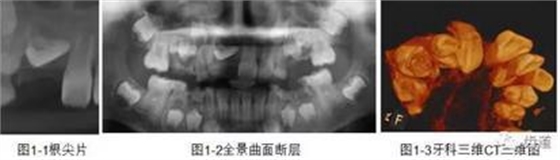

CBCT在牙體牙髓病科治療中,對(duì)牙根周圍的解剖關(guān)系、炎癥病變、囊腫等就能夠輕而易舉的進(jìn)行診斷。甚至與牙齒內(nèi)根管的數(shù)目、走向、分支等都能夠通過(guò)牙科CT進(jìn)行展示,使臨床醫(yī)生的根管治療不再是完全憑手感的“經(jīng)驗(yàn)科學(xué)”。通過(guò)CBCT,還可以對(duì)一些“久治不愈“的疑難病例進(jìn)行檢查和診斷,例如根縱列的診斷、根管內(nèi)異物的定位等,找準(zhǔn)了原因,結(jié)合先進(jìn)的治療技術(shù)因病施治,使疑難病例的治療變的輕松起來(lái)。

1、牙髓根管治療

1)根管治療中牙膠尖充填在CBCT中的影像

2)根管測(cè)量

2、多生牙

多生牙的定位